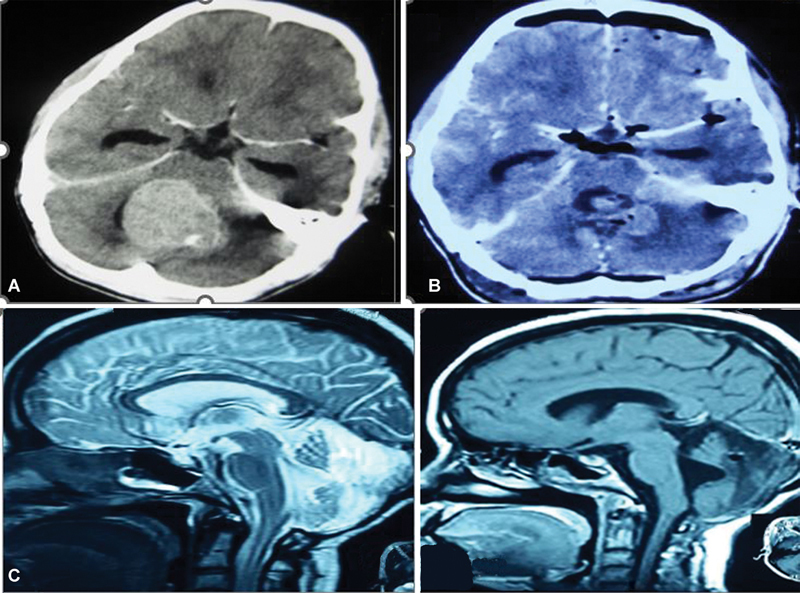

Materials and methods: The study included 60 pediatric patients with a posterior fossa tumor who underwent surgery by a telovelar approach. Detailed pre- and postoperative clinical and radiological evaluations were done. Patients with CMS were analyzed and compared with those without mutism to find risk factors for CMS. The presentation and characteristics of cerebellar mutism were studied along with the following risk factors:Clinical-age, sex, cranial nerve deficit, and adjuvant treatment.Radiological-tumor location, hydrocephalus, brainstem invasion, extent of tumor resection, peduncular and brainstem edema, and atrophy of posterior fossa structures.Pathological-histopathology of tumor.The preoperative, immediate postoperative, and 1-year postoperative imaging results were reviewed to assess the neuroradiographic features in the two groups.

Results: The incidence of this syndrome was 20%. The mutism was accompanied by some neurobehavioral abnormalities ( p -value = 0.05). The most significant finding was the presence of a period of cerebellar dysarthria after the resolution of the muteness ( p -value < 0.001) in all cases. Brainstem and related structures' involvement was the most significant risk factor ( p -value = 0.03). The presence of brainstem and peduncular edema in the immediate postoperative period ( p -value = 0.04) and gross atrophy of posterior fossa structures at 1 year ( p -value = 0.01) showed significance toward the development of CMS. There was delayed neurological recovery in patients with CMS with a poor Glasgow Outcome Score at 1 year of follow-up.

Conclusion: The clinical presentation of this syndrome in context with neuroradiographic features suggests that it results from transient impairment of the afferent and/or efferent pathways of dentate nuclei that are involved in initiating complex volitional movements and are associated with brainstem involvement of tumor and poor functional outcome.